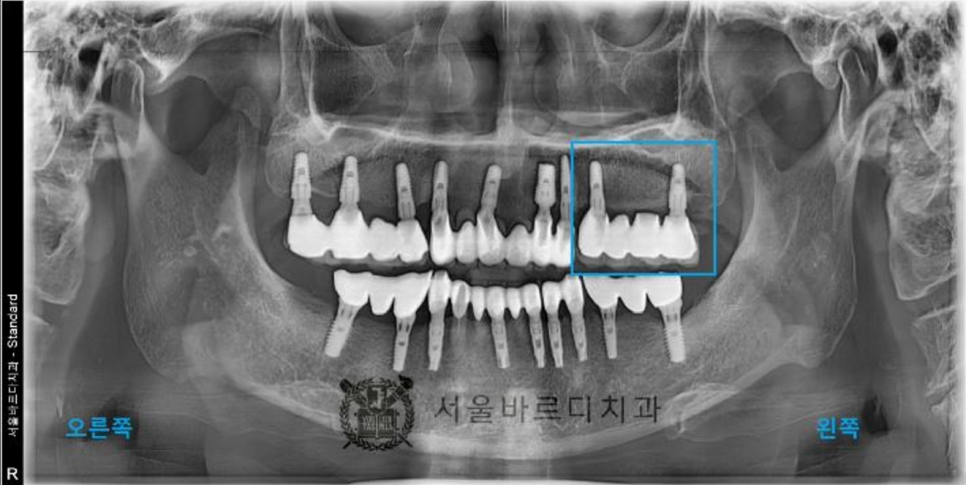

빠진 임플란트와 그 옆에 하나 더 임플란트 시술을 하셨습니다.

임플란트 후에도 수술이 잘 되었는지

파노라마와 3D CT촬영으로 결과를 확인합니다.

기존 보철물보다 임플란트 한 개를 더 추가하여

총 4개의 치아를 회복시켜드렸습니다.

임플란트는 뿌리 부분이 가늘고 머리가 크기 때문에

힘을 더 잘 받기 위해 4개의 치아를 묶어서 제작하였습니다.